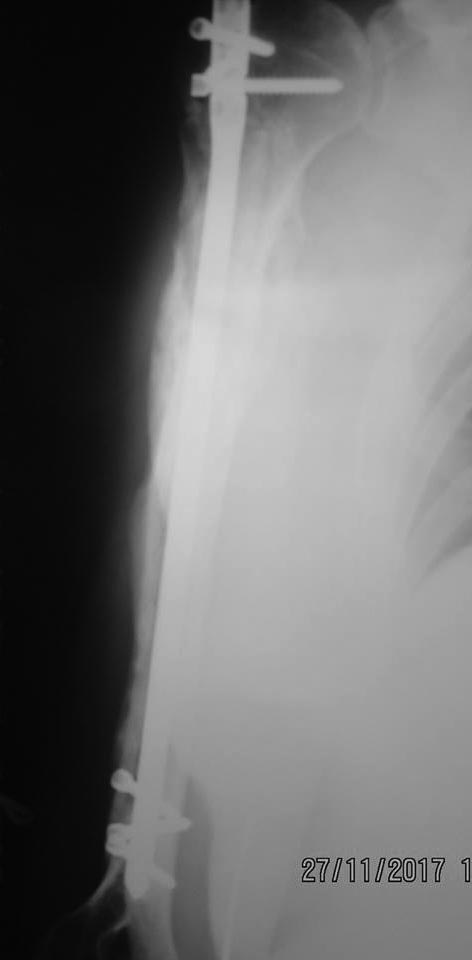

Пациентка 47 лет; травма – 15.07.17, операция – 24.07.17. В результате реабилитационного лечения: отведение - 45 гр., сгибание -75 гр.

Выждать до полной консолидации перелома, удалить стержень и провести редрессацию. По другому кажется не получится.

Импиджмент. Глубже нужно было вводить. Возможно есть проблемы с сухожилием надостной

Думаю, при сращении провести удаление стержня, редрессацию под наркозом, можно артроскопическую диагностику и артроскопическую субакромиальную декомпрессию сделать. Если есть разрыв ротаторной манжеты, то подшить ее .

Точка введения оччччень латеральная. Откуда и проблемы.

Для академизма можно сделать снимок в максимальном отведении. А вообще - да, если срослось, то удалять. Если не срослось, а движения нужны - пересинтезировать без выстояния имплантата.

хотя и так видно, что не сросся, если убрать стержень, очистить ложный сустав до «росы «, положить туда какой нибудь стимулятор сращения, или губчатую кость, или прп и зафиксировать надежно длинной пластиной с угловой стабильностью будет вообще шикарно, можно на следующий день после операции, если анестезиолог заранее наложит межлестничный катетер против боли, начинать на шине с мотором разрабатывать отведение и сгибание

На мой взгляд - сравнить рентгенограммы в динамике для решения вопроса срослось или нет, если срослось - удалить стержень и разбираться с манжетой ротаторов (артроскопия).